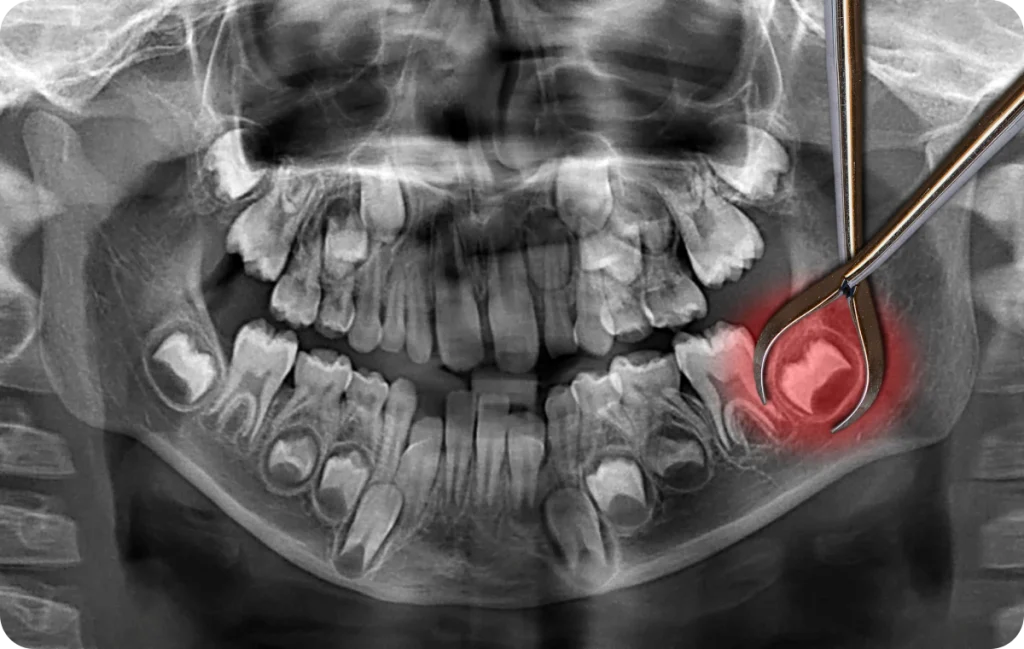

Les examens radiographiques sont essentiels pour évaluer cette situation et orienter la décision de suivi ou de prise en charge.

La radiographie panoramique est couramment utilisée pour évaluer les dents de sagesse. Elle offre une vision globale des mâchoires et permet d’analyser la position des dents, leur orientation et leur proximité avec les structures voisines. Cet examen aide à établir un diagnostic précis et à déterminer la conduite à tenir.